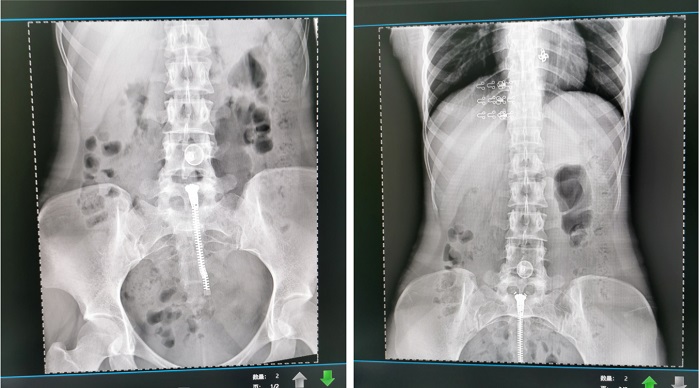

普利德懸吊DR采用高品質(zhì)平板探測器,滿足人體頭部、胸部、腹部、腰椎、四肢等部位的數(shù)字?jǐn)z影檢查,成像速度快,圖像質(zhì)量高,可對肺野內(nèi)細(xì)微結(jié)構(gòu)顯示清晰,病變檢出率高,而且降低受檢者所接受的輻射劑量,這些優(yōu)勢在體檢篩查中對早期發(fā)現(xiàn)病變具有重要的意義。